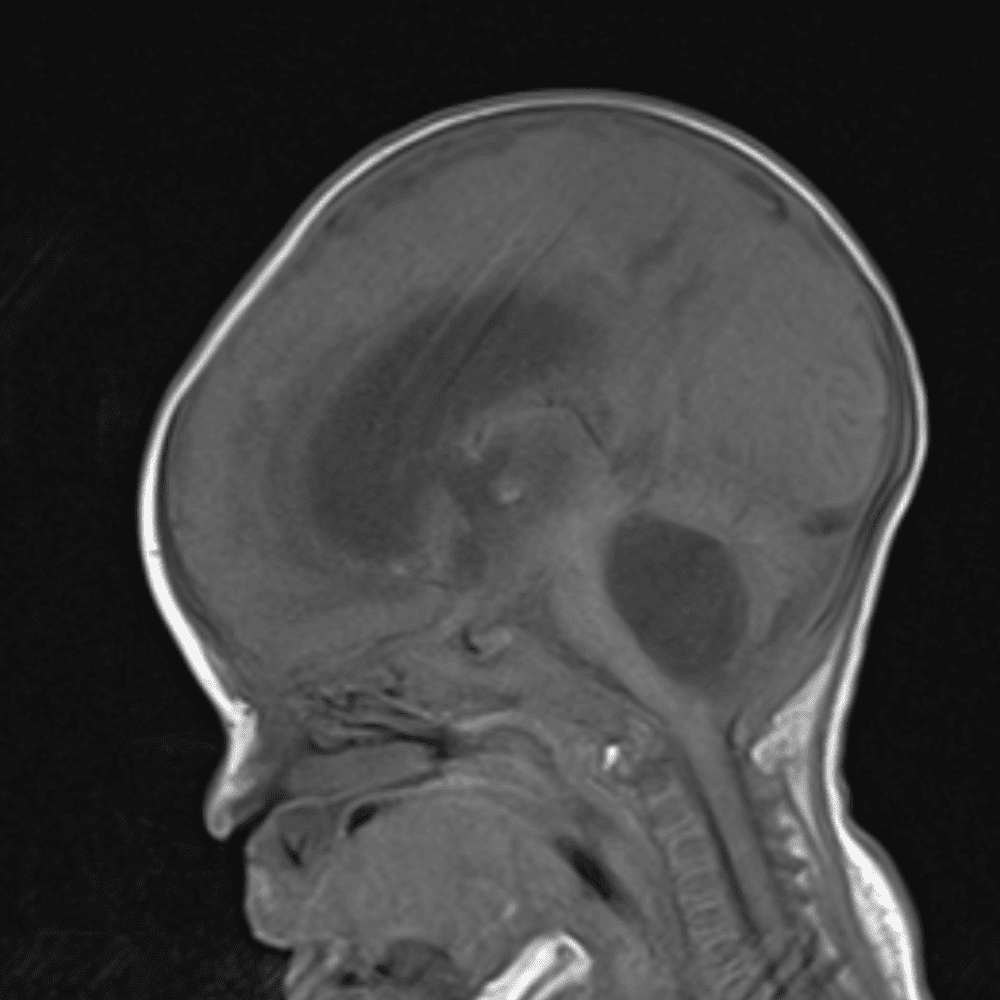

๋‹น์ง ์‹œ ํ”ํžˆ ๋ณผ ์ˆ˜ ์žˆ๋Š” ์‚ฌ๋ก€์˜ ์ „ํ˜•์ ์ธ ์˜ˆ๋ฅผ ํฌํ•จํ•ฉ๋‹ˆ๋‹ค.

39 ์‚ฌ๋ก€